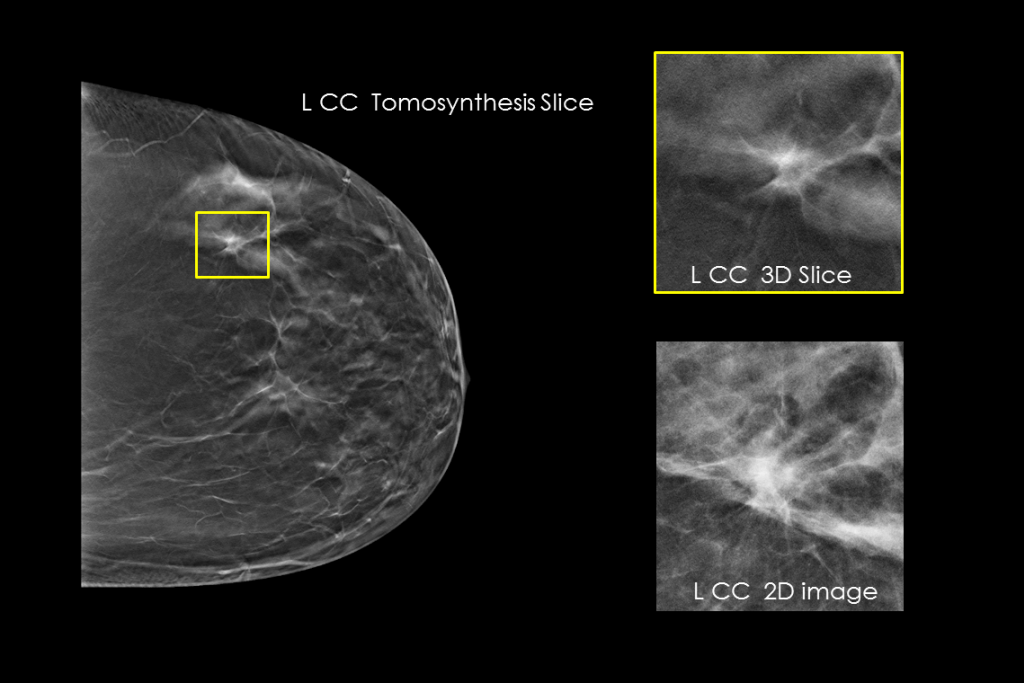

Imagens clínicas de mamografia com lesão suspeita